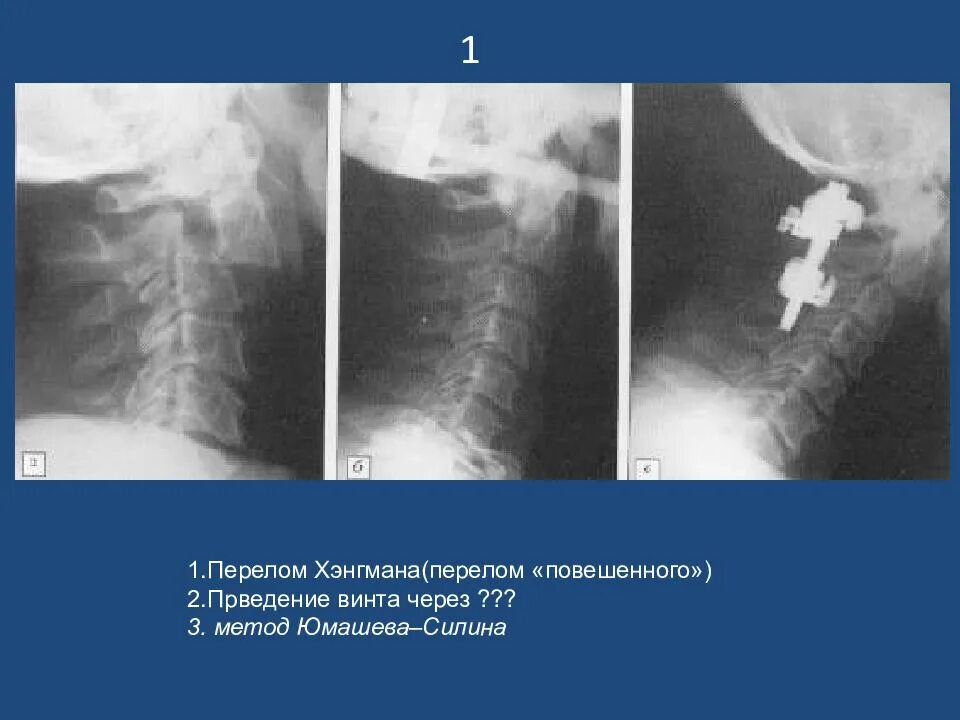

Как выглядит подвывих